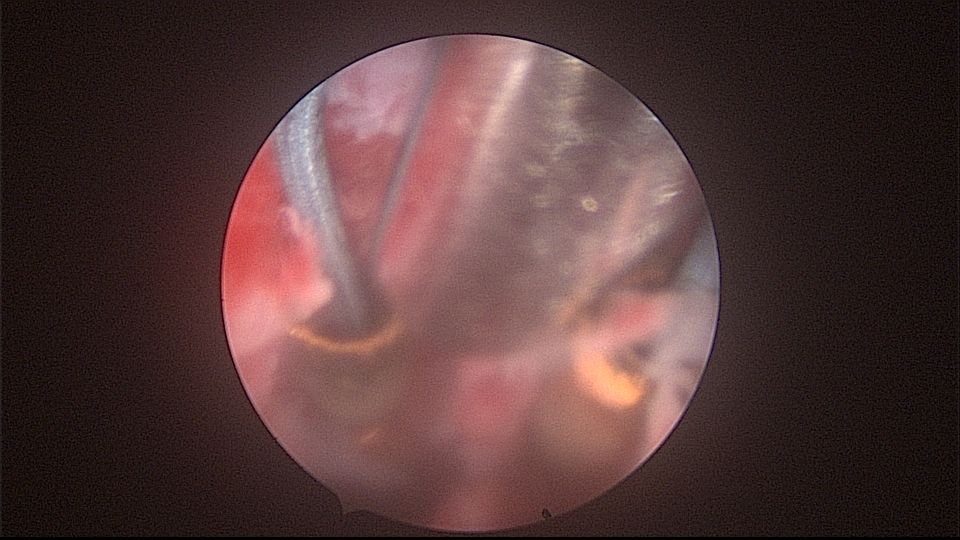

患者52岁,G2P1,顺产1次。安环27年,外院取环失败。病人肥胖,子宫极度前倾前屈位,宫腔镜见宫颈管组织杂乱,宫颈管上段右前壁见假道,膨宫不良,视野模糊,寻找宫腔方向困难,准备B超监护过程中,拆走扩阴器,腹部下压子宫,终于寻找到了宫颈内口,看到了爱母环下端,异物钳牵拉出节育环,再次探查宫腔,无其他异常。